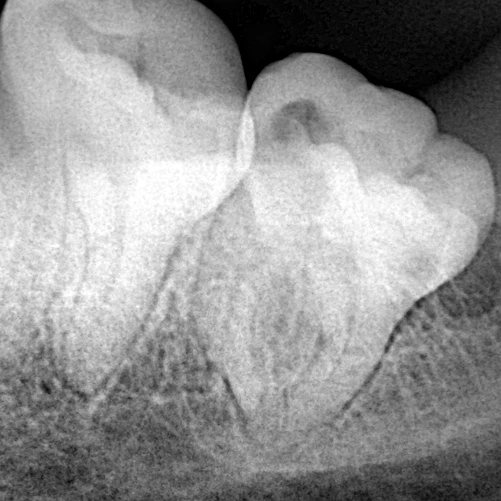

Patient complain from eevere night pain in her lower 8 from 3 days ago

Instrumentaion with edge endo file

Obturation with One-fil bioceramic sealer